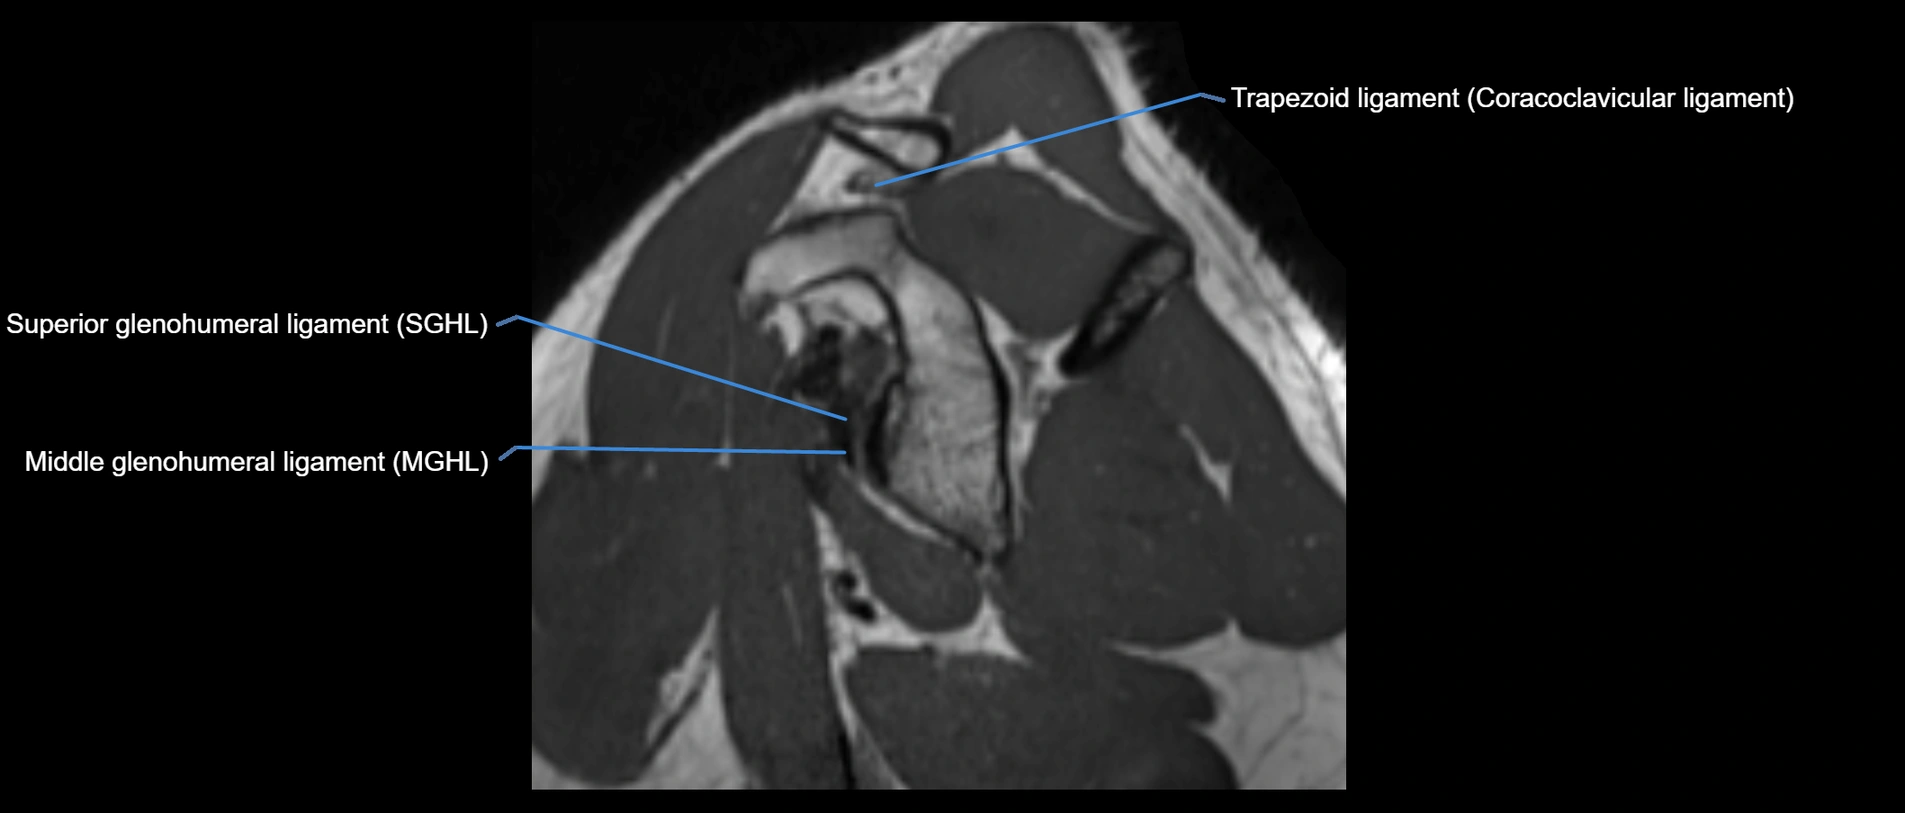

CT image

image